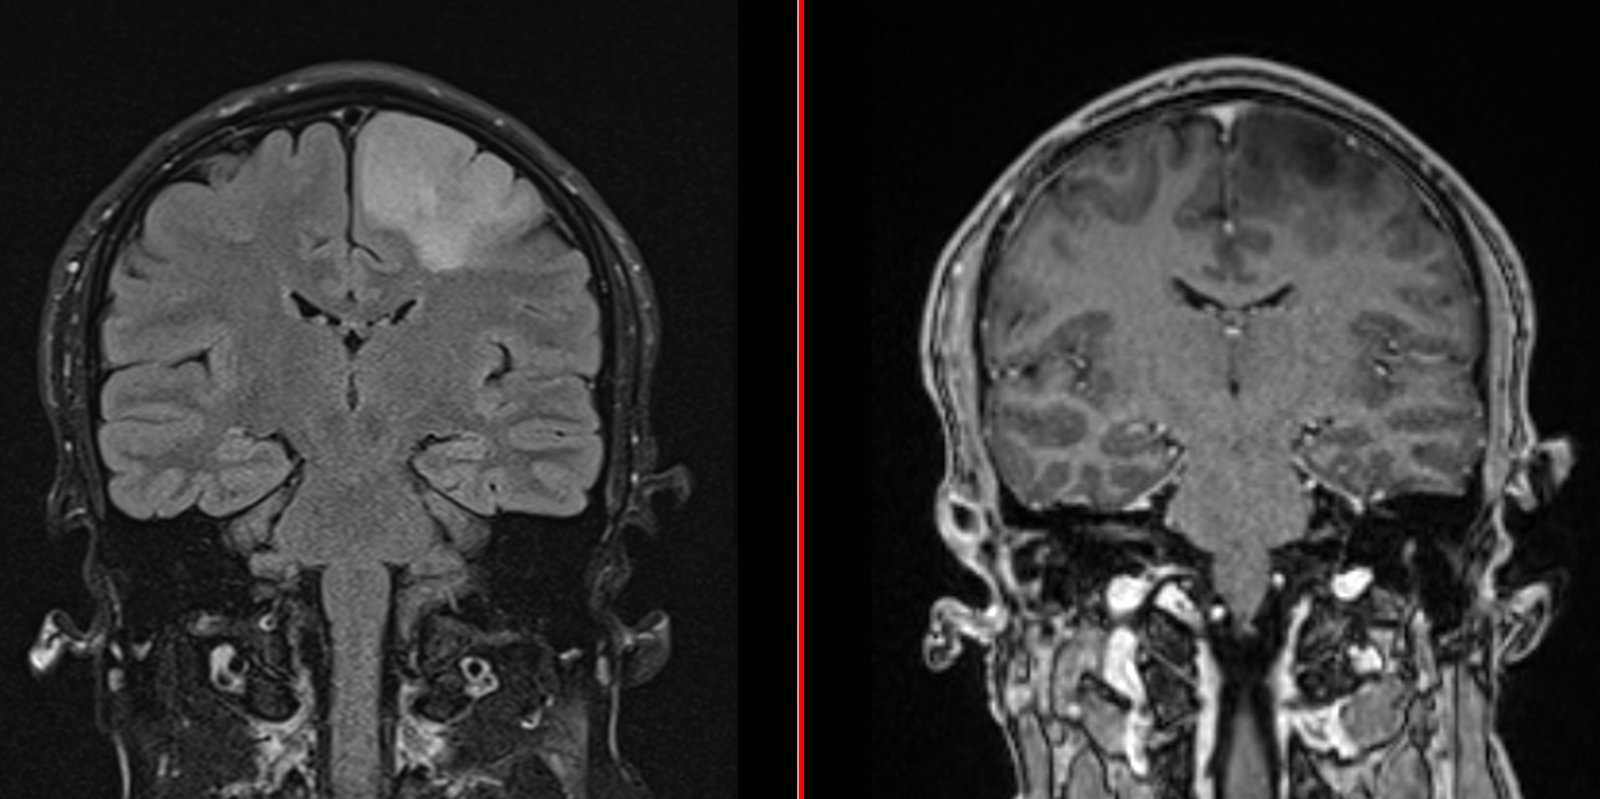

RMN cerebral cu contrast – metoda standard pentru caracterizarea glioamelor. Glioamele de grad mic apar ca leziuni hipointense pe T1, hiperintense pe T2, fără captare de contrast. În mod uzual se consideră că dacă un gliom de grad mic are o zonă cu priză de contrast pe RMN el este de grad III – anaplazic (grad înalt).

Oligodendrogliom temporal stâng – spectroscopie RMN

Oligodendrogliom temporal stâng